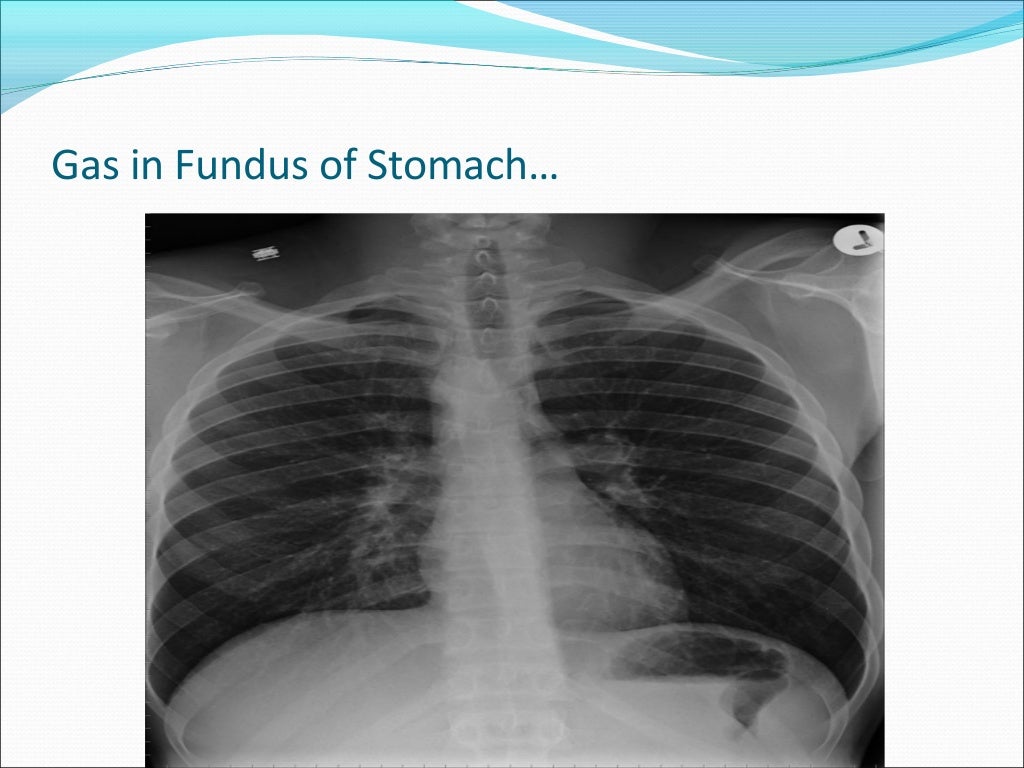

Gas Under Diaphragm Final Year MB BS Lecture Gas Under Right Dome Of Diaphragm Free air under the diaphragm: The standing chest radiograph showed gas under the right diaphragm , and. This condition is usually asymptomatic. There are many possible causes of a raised hemidiaphragm such as damage to the phrenic nerve, lung disease causing volume loss, congenital causes such as a diaphragmatic hernia, or trauma to the diaphragm. Right hemidiaphragm elevation is a. Gas Under Right Dome Of Diaphragm.

Gas Under Diaphragm Final Year MB BS Lecture Gas Under Right Dome Of Diaphragm Free air under the diaphragm: The standing chest radiograph showed gas under the right diaphragm , and. There are many possible causes of a raised hemidiaphragm such as damage to the phrenic nerve, lung disease causing volume loss, congenital causes such as a diaphragmatic hernia, or trauma to the diaphragm. Plain xray of the abdomen in erect posture showed gas. Gas Under Right Dome Of Diaphragm.

Gas Under Diaphragm Final Year MB BS Lecture Gas Under Right Dome Of Diaphragm This condition is usually asymptomatic. Plain xray of the abdomen in erect posture showed gas under the right dome of. There are many possible causes of a raised hemidiaphragm such as damage to the phrenic nerve, lung disease causing volume loss, congenital causes such as a diaphragmatic hernia, or trauma to the diaphragm. The standing chest radiograph showed gas under. Gas Under Right Dome Of Diaphragm.

Gas Under Diaphragm Final Year MB BS Lecture Gas Under Right Dome Of Diaphragm This condition is usually asymptomatic. There are many possible causes of a raised hemidiaphragm such as damage to the phrenic nerve, lung disease causing volume loss, congenital causes such as a diaphragmatic hernia, or trauma to the diaphragm. Plain xray of the abdomen in erect posture showed gas under the right dome of. Free air under the diaphragm: Right hemidiaphragm. Gas Under Right Dome Of Diaphragm.

Gas Under Diaphragm Final Year MB BS Lecture Gas Under Right Dome Of Diaphragm Plain xray of the abdomen in erect posture showed gas under the right dome of. The standing chest radiograph showed gas under the right diaphragm , and. There are many possible causes of a raised hemidiaphragm such as damage to the phrenic nerve, lung disease causing volume loss, congenital causes such as a diaphragmatic hernia, or trauma to the diaphragm.. Gas Under Right Dome Of Diaphragm.